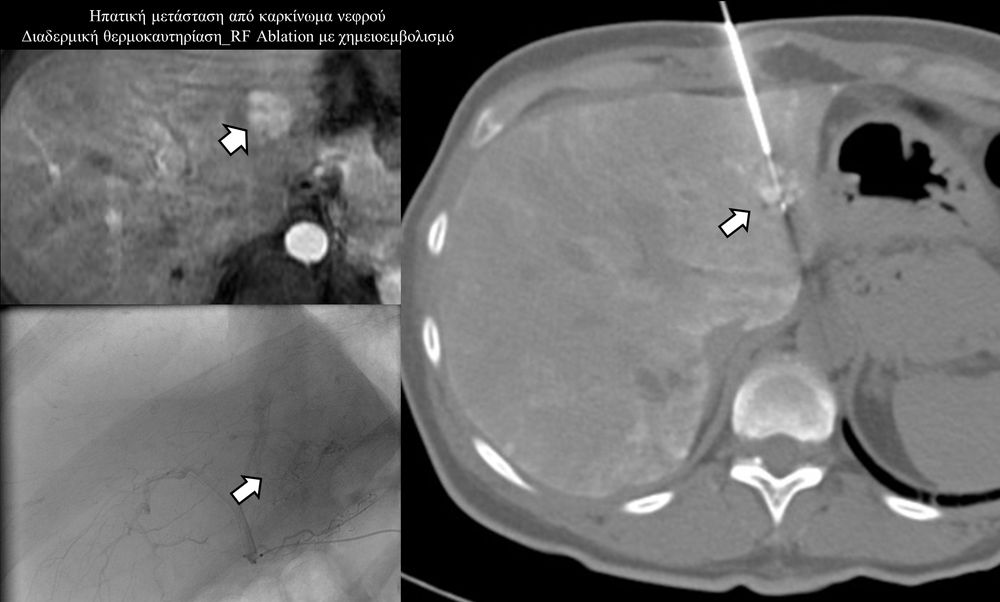

Πρόκειται για την πιο σύγχρονη τοπική θεραπεία όγκων του ήπατος, του νεφρού, του πνεύμονα, των οστών και των όγκων μαλακών μορίων. Παθοφυσιολογικά βασίζεται στην τοπική καταστροφή των καρκινικών κυττάρων με τη δημιουργία ιδιαίτερα υψηλών θερμοκρασιών εντός του όγκου. Αυτό επιτυγχάνεται με τοποθέτηση ειδικών ηλεκτροδίων εντός του όγκου υπό ακτινολογική καθοδήγηση (αξονικός τομογράφος ή υπέρηχος). Τα ηλεκτρόδια αυτά παράγουν υψηλή θερμοκρασία είτε με τη βοήθεια ραδιοσυχνοτήτων (RFablation), είτε με τη βοήθεια μικροκυμάτων (MWablation) και προκαλούν πηκτική νέκρωση των καρκινικών κυττάρων χωρίς να επηρεάζουν τα φυσιολογικά κύτταρα.Το αποτέλεσμα είναι μόνιμο.